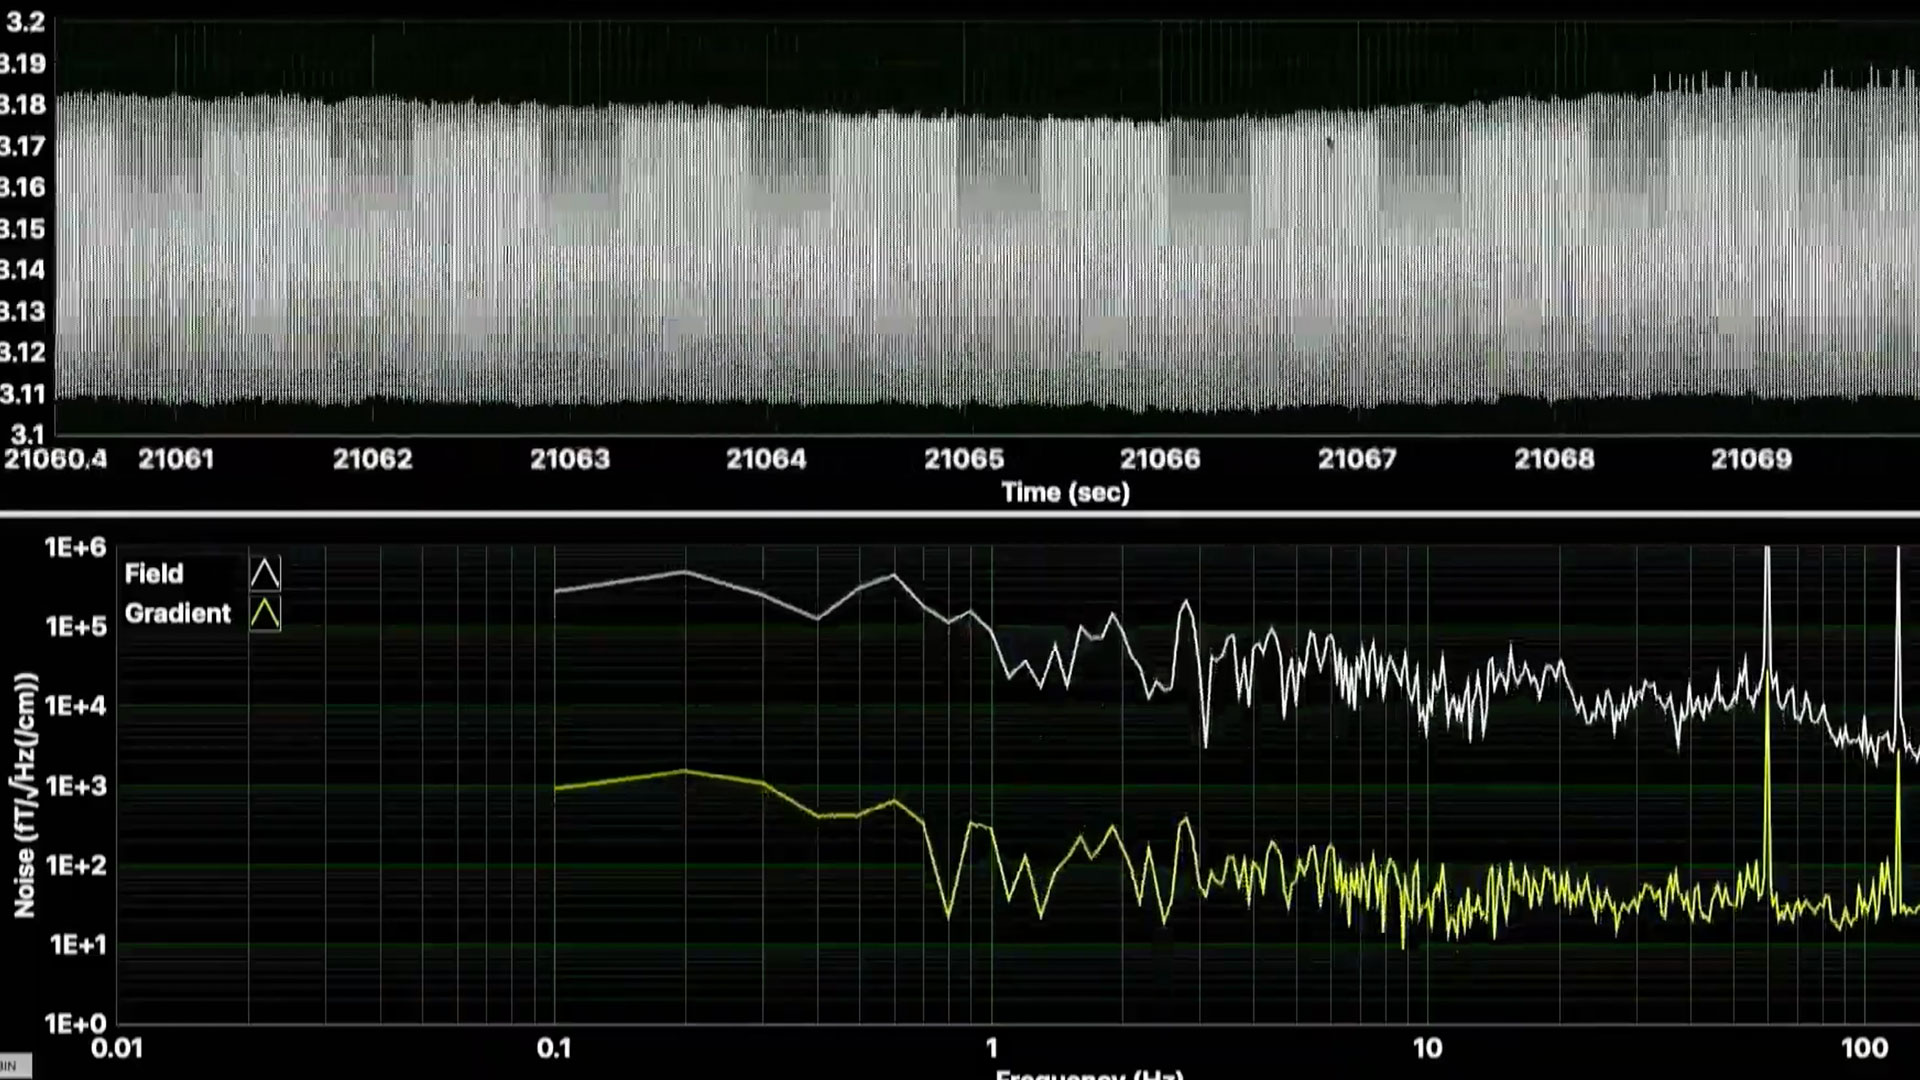

SRI主導のチームが生体磁気信号を検出する磁気センサーを実証

AMBIIENTは、いくつかの病状を診断できる信号を分析する